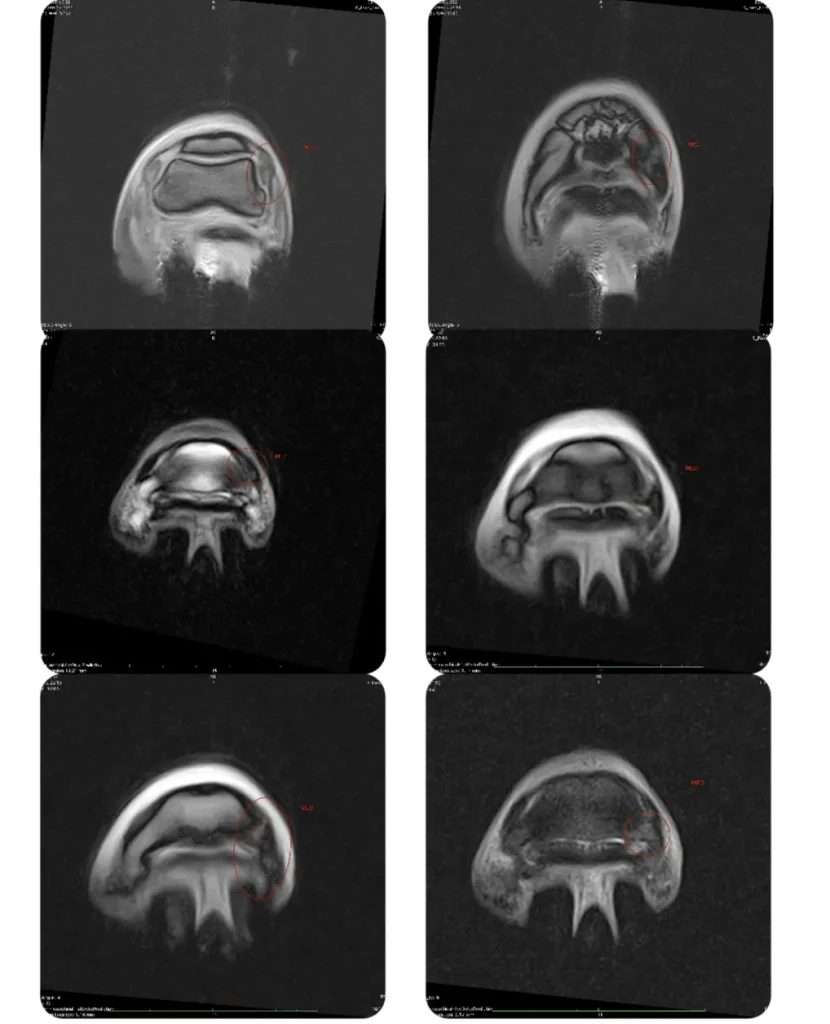

- Other advanced tests, such as scintigraphy and magnetic resonance imaging, in collaboration with specialised equine veterinary hospitals.